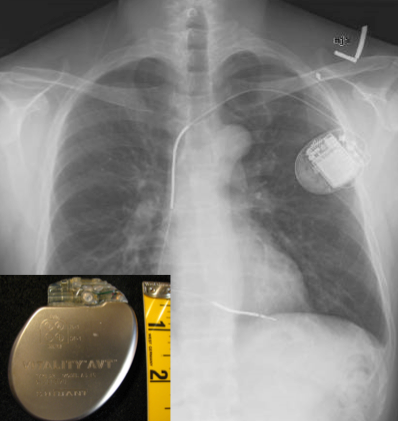

Peverley is in the midst of a battery of testing to determine what happened, and if there’s any damage from his collapse and resuscitation. An EKG to determine what heart rhythm he’s in, an echocardiogram (ultrasound of the heart), possibly another catheterization and electrophysiology study, and continuous monitoring in case he develops another arrhythmia while he’s admitted to the hospital. Plus of course a chest x-ray to make sure he doesn’t have any broken ribs from the CPR (which is notoriously brutal). The problem with sudden cardiac arrest is that it can happen again. If whatever caused it can be identified and corrected, great. Having said that, most people who go into the hospital with sudden cardiac arrest come out with an implantable cardioverter-defibrillator (ICD). Even if testing can identify a reversible cause (like something that can be ablated), it could happen again. The only way to ensure you get prompt defibrillation no matter where you are is to carry your defibrillator inside your chest. Having an ICD makes a hockey career difficult – you have to worry about dislodging the leads every time you get plastered into the boards (or plaster someone else into the boards).